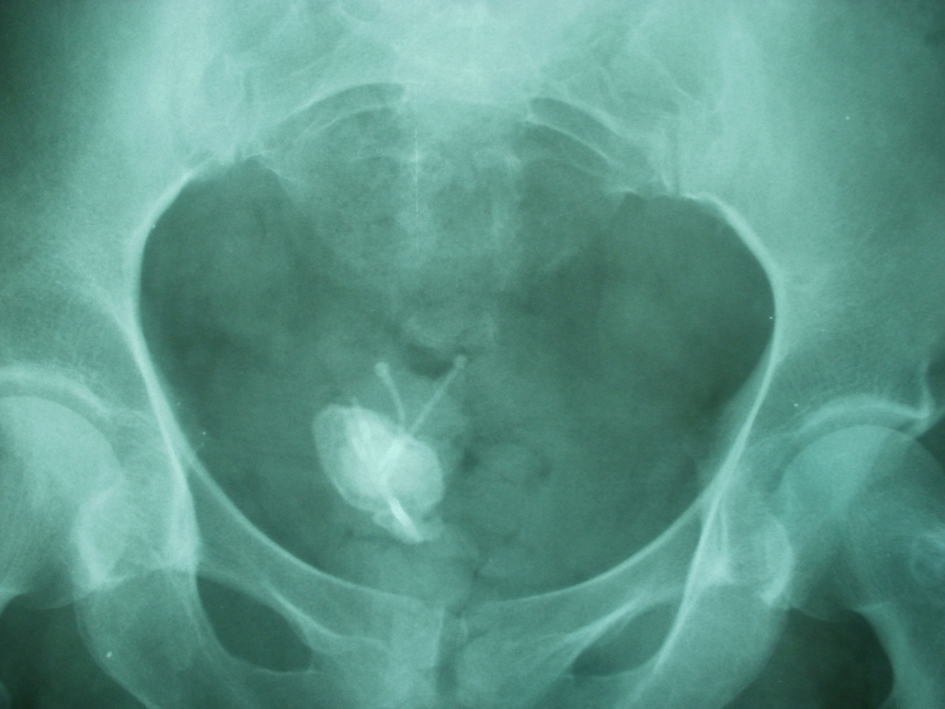

The patient’s medical history indicated that a copper-T IUCD had been inserted in 1999, 3 months following her third normal vaginal delivery. She had unexpectedly conceived again 4 years after insertion and had a normal vaginal delivery without any complication. It was assumed that the IUCD had fallen out and another copper-T IUCD was inserted 3 years after her fourth delivery. As per records both devices were placed correctly in the uterus and the procedures were uncomplicated. Hysterectomy was done in 2011 and it was also assumed that the 2nd IUCD was removed with hysterectomy. Pelvic examination was normal. A plain abdominal radiograph showed the presence in the pelvis of a large stone opacity with dimensions of 3.9 × 3.4 cm around the horizontal limbs of both double IUCD (Fig. 1) which was confirmed by pelvic ultrasonography. Cystoscopy confirmed the presence of two intravesical IUCD, complicated by stone which was fragmented endoscopically using stone crushing forceps. Both fragmented calculus and IUCD were removed cystoscopically by a grasping forceps (Fig. 2). The patient was discharged one day after removing the IUCD, with uneventful evolution.

![]() Click for large image | Figure 1. X-ray of the pelvis demonstrates two intrauterine contraceptive devices (IUCD) within the pelvic cavity with calculus formation on the horizontal limb of both IUCD. |